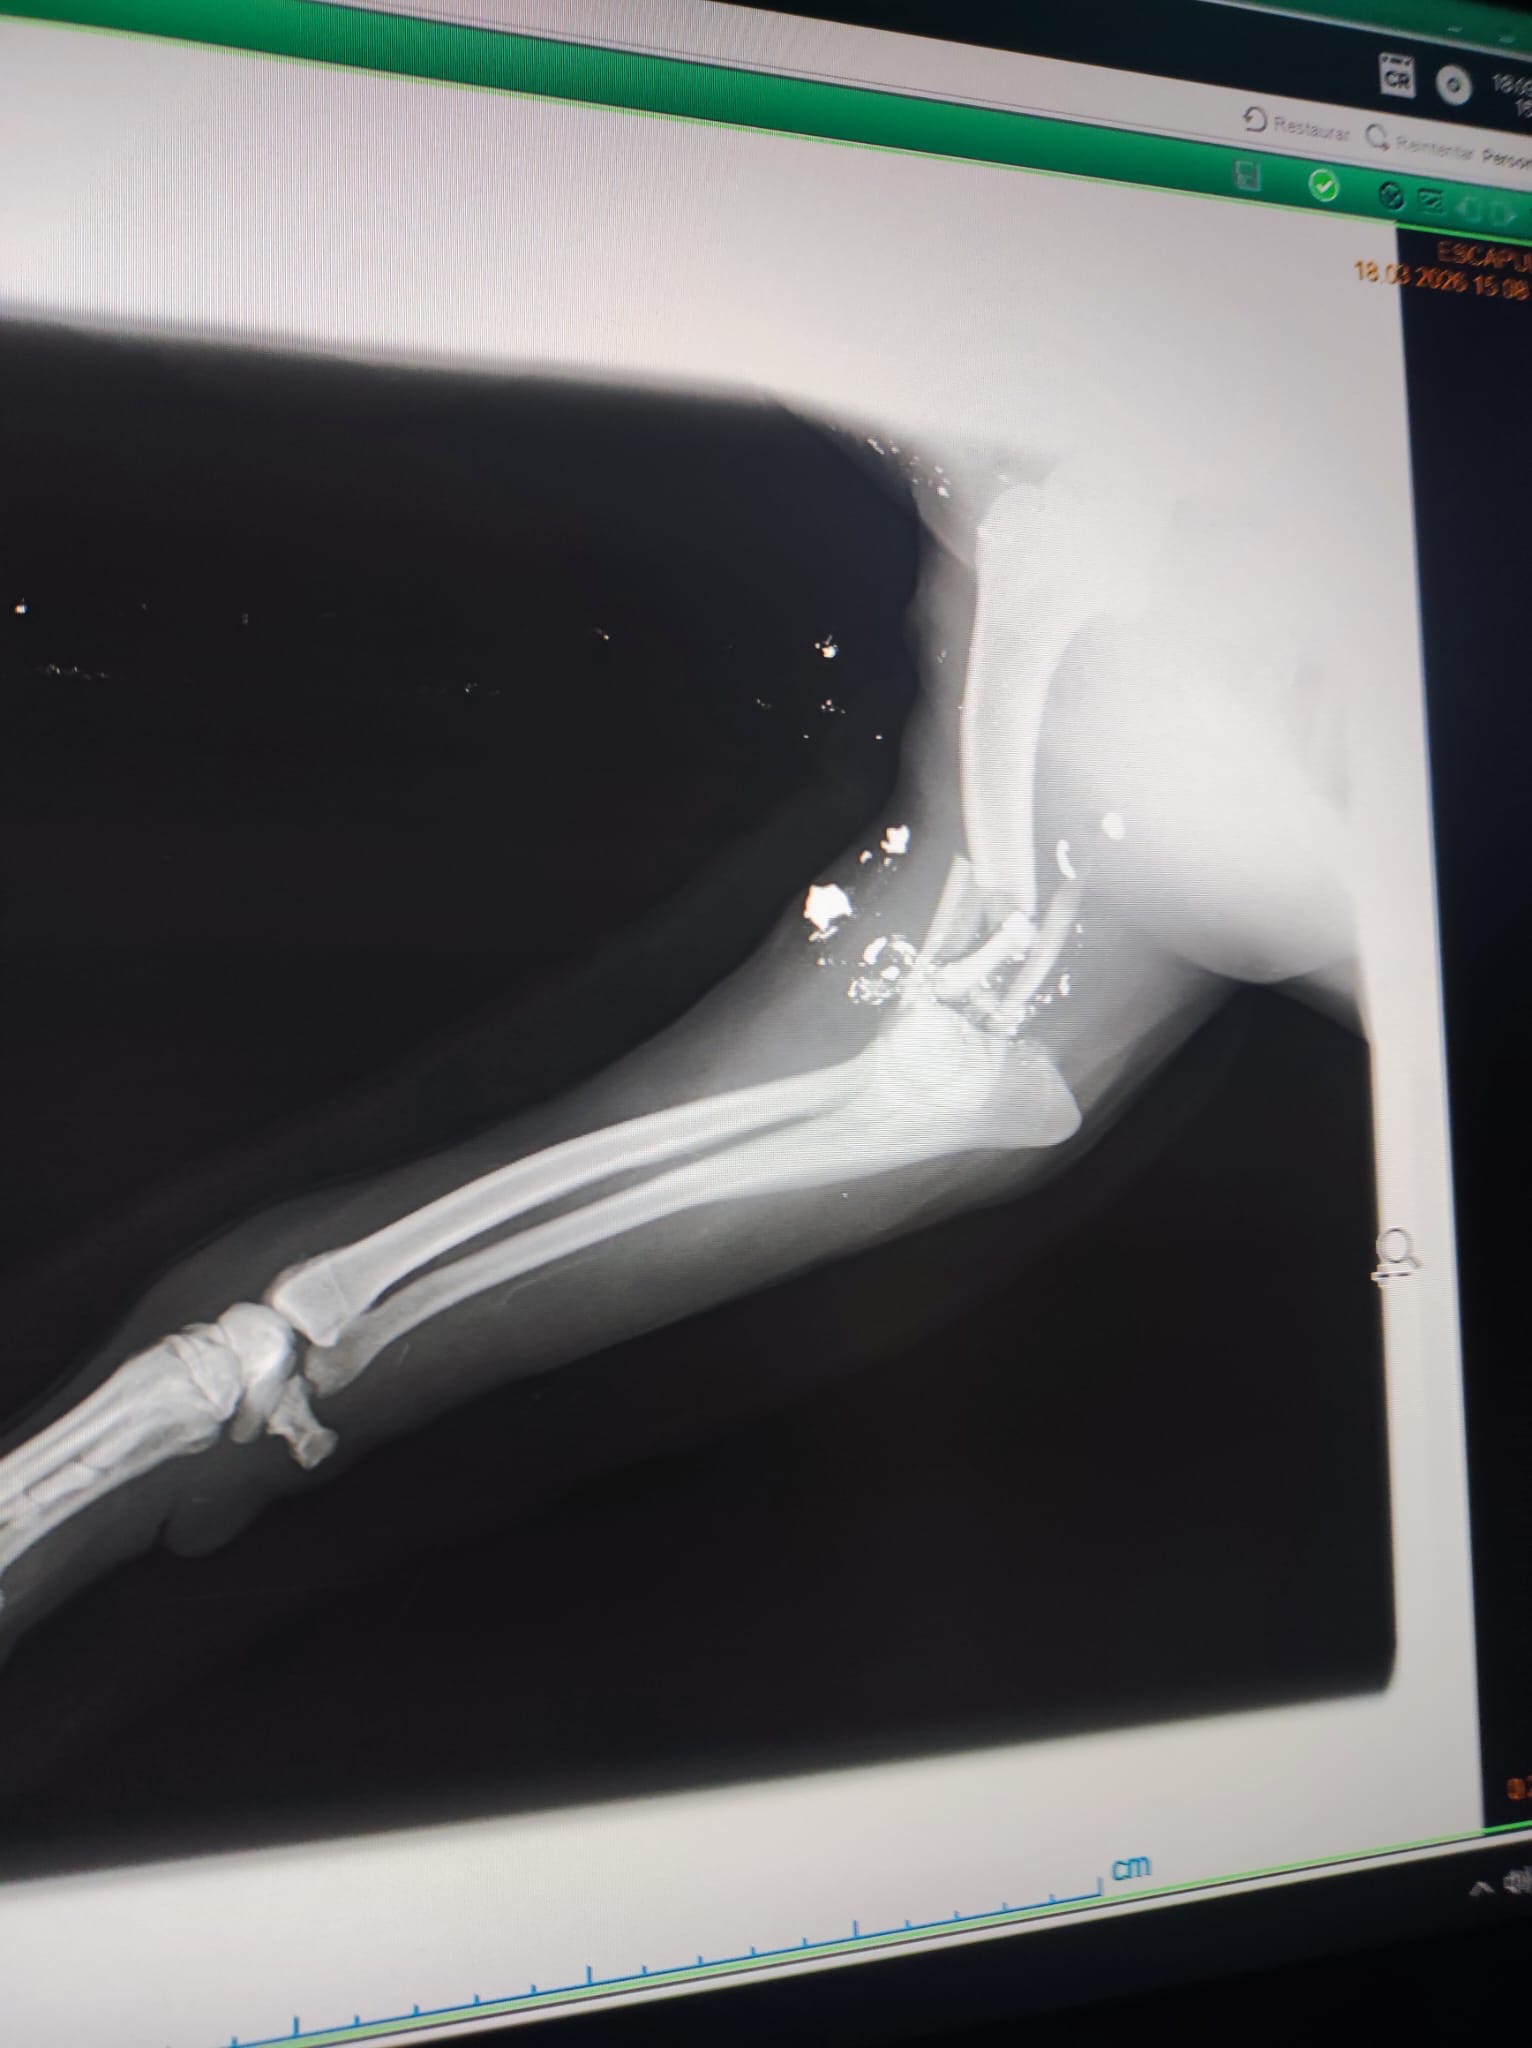

Sonia und Carmen haben einen Beagle mit einem zerschossenen Bein gefunden. Sie sind sofort mit ihm in die Tierklinik gefahren. Der Tierarzt hat einige Splitter und Kugeln aus der Schusswunde am Ellenbogen entfernt. Nun bekommt der Hund Antibiotika, Entzündungshemmer und Schmerzmittel. Eine Operation ist nach dem jetzigen Stand nicht möglich. Freitag findet ein Kontrolltermin in der Klinik statt. Der Beagle ist ein Rüde und lt. Tierarzt ca. sieben Jahre alt, wobei er deutlich älter wirkt. Wir werden weiter berichten. Ein großes Danke wieder einmal an Sonia und Carmen in Galizien.